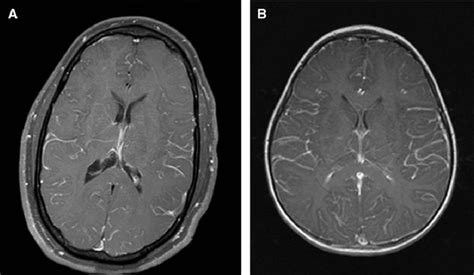

Magnetic Resonance Imaging (MRI)

MRI scans of the brain and spine are crucial for visualizing the leptomeninges and detecting any abnormalities, such as enhancement of the meningeal layers or the presence of tumor nodules. Gadolinium contrast is often used to improve the detection of these changes.